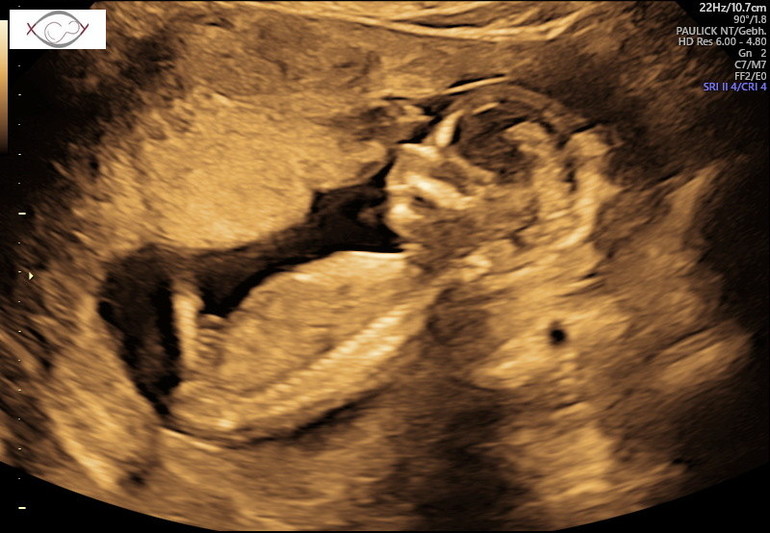

Посещение и назначения врачей (стоматологи, кардиологи и проч.)Сегодня ездила на первый скрининг. Естественно волновалась всё время пока ждала. Ожидание мне вообще не легко даётся, хочу всё и сразу🤪Как в фильме Человек с бульвара Капуцинов: "Джонни, сделай мне монтаж" 🤣🤣🤣 А ещё почему то больше пугает когда прям всё черезчур хорошо. Надо тут же выискивать что то, переживать, как то не укладывается в голове что всё хорошо🤷♀️Ещё 2 недели назад мой гинеколог развёл руками над моими анализами и произнёс" мне особо нечего Вам сказать, у Вас идеальная беременность" 🤷♀️ И вот сегодня в пренатальном центре - развитие день в день, кровоток отличный, всё как по книжке. Риски трисомии, конечно, есть, всё таки возраст, но это стандарт, совсем без рисков не бывает. Но нипт на всякий який, конечно, сдала🤪 Плюс уже пол хоцца узнать, лопну от любопытства. На УЗИ кроха стеснялся и прятался, разбудили его 😅. А меня всё дальше начинает тревожить, что слишком хорошо всё, так не бывает😬😬😬 С другой стороны, только второй триместр начался, цвяточки ещё впереди😬